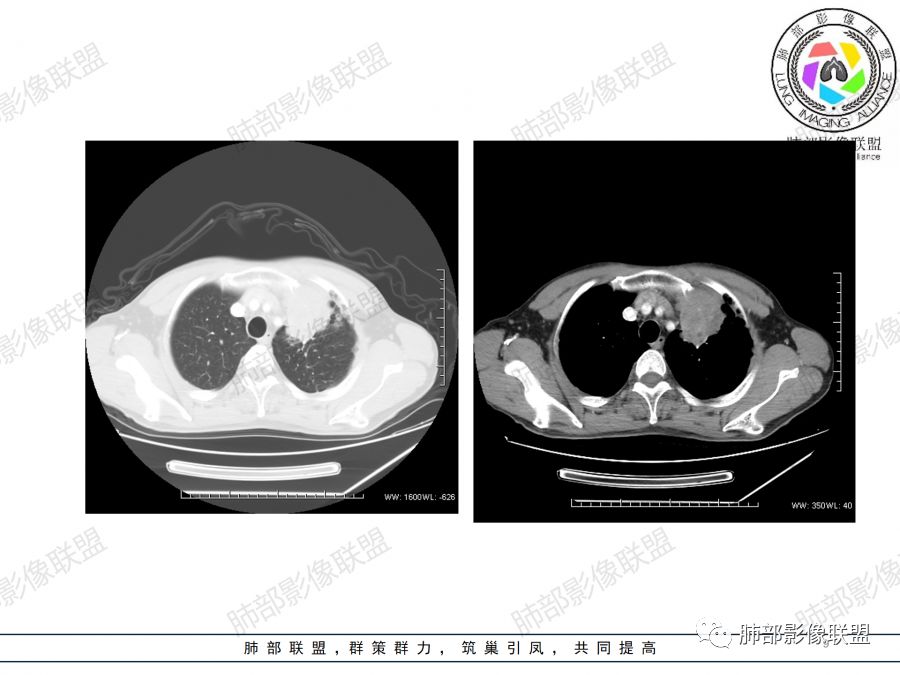

男,47岁,咳嗽咳痰一月。病灶位于左内乳动脉内缘,定位肺内,呈团片状异常密度影,整体沿支气管气管束走形分布,由肺门达胸膜下,于近肺门侧病灶形态相对较小,病灶远端相对较大,病灶整体密度偏均匀,强化偏明显,病灶内见多发支气管扩张并粘液栓形成,且扩张支气管粗细不均,直达病灶以远,病灶内血管走形正常、粗细均匀,病灶周围见边缘模糊磨玻璃及少许腺泡结节。左肺门及纵隔略大淋巴结,左侧胸膜局限性增厚。诊断:左肺上叶前段异常密度影,炎性肉芽肿性病变可能,结核不能除外,建议穿刺活检除外恶性肿瘤。

支持肉芽肿性炎,肺癌待排,穿刺活检。

病理结果

肺结核